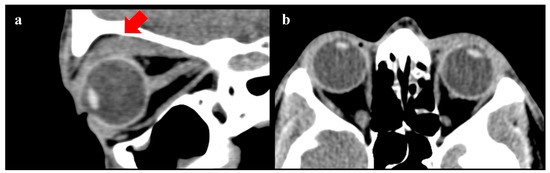

| Joseph A. et al. (2018) [24] | Book chapter | “…Eyelid retraction, lid lag on downgaze and lagophthalmos, and decreased convergence may be found in patients with thyroid-related orbitopathy. Blepharoplasty should be reserved for patients with quiescent disease and undertaken after any proptosis, motility dysfunction, and eyelid retraction have stabilized for 6 months to 1 year or have been definitively treated. In patients with suspected thyroid eye disease, referral to an endocrinologist or internist may be necessary for appropriate systemic workup, including serum thyroid hormone levels (triiodothyronine [T3], levorotatory thyroxine [T4], thyroid stimulating hormone [TSH]). Orbital computed tomography may demonstrate enlargement of the extraocular muscles and increased orbital fat when systemic signs are completely lacking early in the course of the disease…” |

| Kwitko G.M. et al. (2021) [28] | Review | “...Most contraindications for ptosis surgery revolve around the exposure of the cornea. Conditions like thyroid orbitopathy, progressive external ophthalmoplegia, or loss of Bell’s phenomenon can make patients more prone to exposure keratopathy after ptosis surgery: a more conservative approach is needed in these patients…CT scan of the orbits should be obtained if an orbital process such as thyroid orbitopathy or an orbital tumor is suspected. Slit lamp evaluation is essential to detect corneal erosions or dry eye…” |